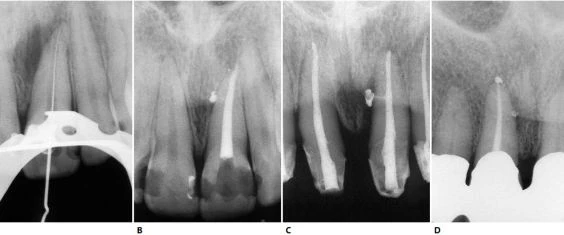

Trên X-quang có thể thấy chân răng hơi cong nhẹ theo chiều gần xa hoặc ngoài trong (hình 5.41).

Hình 5.41. A. Phim X-quang trước điều trị của răng cửa giữa hàm trên bên phải. Lỗ chóp nằm trên cùng một mặt phẳng trên đường đi của tia X: nó có thể đối diện với mặt trong hoặc mặt ngoài. B. Phim X-quang thứ hai chụp theo hướng gần-xa cho thấy đoạn cong đối diện với mặt ngoài. Việc điều trị tủy được hoàn tất, giữ nguyên góc chụp cho phép nhìn thấy được điểm cuối cùng trên X-quang của ống tủy. C. Phim sau điều trị. Lưu ý rằng chỉ với góc chụp này mới thấy được hình ảnh tổn thương nhỏ tại chóp chân răng. D. Phim sau điều trị được chụp theo tiêu chuẩn hình chiếu. Lưu ý rằng vật liệu trám ống tủy dường như bị ngắn đi chừng 2mm và tổn thương cũng đã lành.